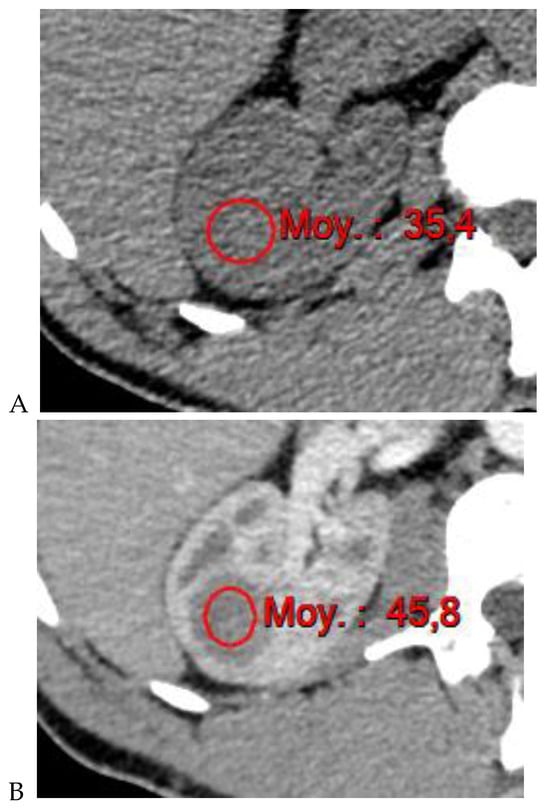

Figure 4.

Multiphasic CT enhancement of a papillary renal cell carcinoma in the middle part of the right kidney of a 63-year-old woman. (A) Mean unenhanced attenuation was 35 HU. (B) Mean corticomedullary phase attenuation was 45 HU. (C) Mean nephrographic phase attenuation was 59 HU. (D) Mean excretory phase attenuation was 65 HU.